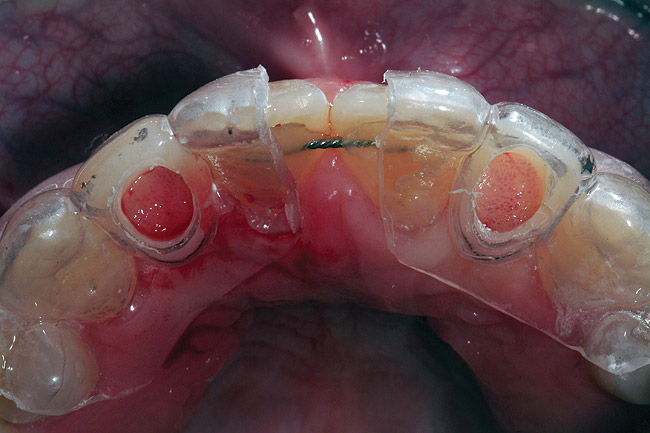

A 19-year-old non-smoking female presented for tooth replacement at the maxillary right and left lateral incisors, which were congenitally missing (Figure 1). The post-orthodontic result was adequate for the placement of 3-mm one-piece small-diameter implants. The preoperative radiographs can be seen in Figure 2 and Figure 3. The pretreatment clinical view in Figure 4 and Figure 5 shows the small intertooth space present in the lateral incisor areas. One of the most challenging tasks with congenitally missing lateral incisor cases is to create an acceptable soft tissue emergence profile from a crestal profile that is flat from the mesial of the canines to the distal of the centrals (Figure 4 and Figure 5). After pretreatment planning which consisted of a complete medical and dental history, radiographic analysis, and upper and lower study models mounted by a facebow transfer technique, the fabrication of a TempStent II surgical guide was completed. Figure 6 and Figure 7 show the occlusal view of the TempStent II guide on the study cast and in the oral cavity, respectively.

After administration of an appropriate local anesthetic and prior to initial coring of the implant surgical site, procedures were completed to ensure proper implant positioning and creation of the esthetic tissue emergence profile in the crest of the ridge. This was completed by placement of the TempStent II (Figure 8) and then through the occlusal aspect of the surgical guide, marking the crest of the ridge with a #8 round diamond. Once this was completed, creation of the soft tissue emergence profile was then accomplished by placing a football-shaped diamond into the high-speed handpiece, and then outlining the soft tissue to follow the flow of the emergence profile of the canine to the central, outlining the emergence profile of the lateral site, and creating interproximal papillary contours. This shaping of the gingival tissues was then continued to the osseous crest, and the same dimension was carried on to the alveolar structures, thereby taking the biologic width into account. This allowed for a sculpted implant receptacle site for the minimally invasive surgical approach for implant placement. Assessment of the width of attached gingiva should be performed prior to this procedure to ensure that an adequate band will be present at the conclusion. If an inadequate width will remain after coring the site, then a crestal incision and displacement of the keratinized gingiva facially may be a better approach. Based on pre-surgical evaluation, the buccal/palatal dimension of the edentulous ridge was acceptable for this minimally invasive approach, and the minimal amount of bone grafting required to “plump” the facial aspect of the site was easily accomplished by a “pouch” grafting technique to enhance the cosmetic aspect of the case.

Figure 6  Occlusal view, TempStent II Surgical Guide.

Figure 6

Figure 7  Intraoral occlusal view, TempStent II Surgical Guide.

Figure 7

Figure 8  Facial view, TempStent II Surgical Guide.

Figure 8